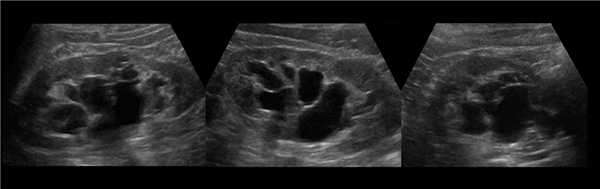

Рисунок. У новорожденного на УЗИ почек определяется гидронефроз (1) и расширенный мочеточник (2) справа. В мочевом пузыре двустороннее уретероцеле (3). При исследовании левой почки структурных изменений не выявлено.

Рисунок. На УЗИ определяется удвоенная чашечно-лоханочная система, расширена лоханка верхнего сегмента (1) и мочеточник на всем протяжение (2, 3), в мочевом пузыре уретроцеле (4). Полное или неполное удвоение чашечно-лоханочной системы возможно увидеть с помощью КТ-урографии.

Рисунок. Двустороннее уретероцеле на УЗИ: в режиме ЦДК из верхушек уретероцеле определяется выброс мочи.

Рисунок. На УЗИ в уретероцеле определяется гиперэхогенная структура с акустической тенью — камень. Уретероцеле может являться одним из факторов, способствующих камнеообразованию.